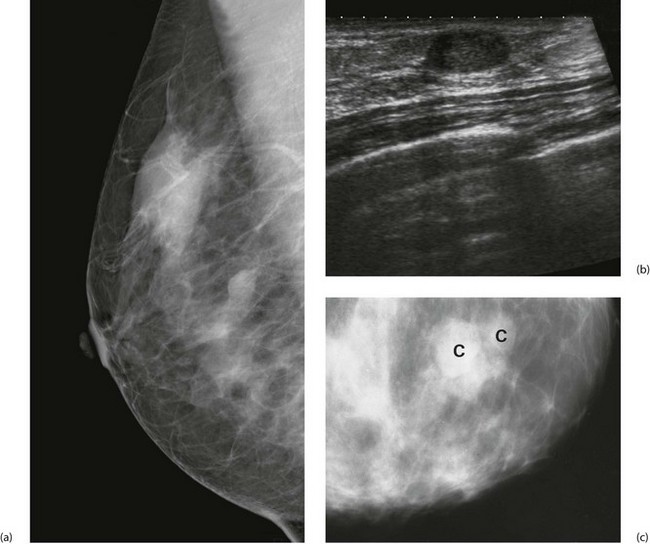

Ultrasound has long been used to distinguish solid lesions from cysts and has a specificity of 100% for this. Modern B-mode ultrasound demonstrates breast anatomy in great detail and is complementary to mammography. Benign lesions can be distinguished from malignancy with a sensitivity for cancer of at least 85%. Ultrasound can accurately measure the size of a cancer (Fig. 45.7) and can guide percutaneous needle biopsies and cyst aspiration (Fig. 45.8).

Cyst formation is more prevalent over the age of 40 years and in perimenopausal women. Cysts may present symptomatically as single or occasionally multiple lumps. Cysts develop from lobules and are fluid-filled spaces. Microcysts are part of the involutionary process and may coalesce to produce a larger cyst which presents as a smooth, round palpable lump. Larger cysts may be tense, tender and fluctuant with the texture of a table tennis ball. Cysts can usually be diagnosed clinically and are readily confirmed with ultrasonography; they are usually recognisable on a mammogram. Simple cysts can be aspirated under ultrasound control or freehand. Provided the cyst fluid is not blood-stained, there is no residual lump post aspiration and there are no sonographically suspicious features, patients can be discharged without further follow-up, although cysts can recur or new cysts develop (see Fig. 45.21). Cysts are uncommon over the age of 60 years unless the patient is taking HRT. Under these circumstances it is important to exclude an intracystic papilloma, intracystic carcinoma or a cystic carcinoma.